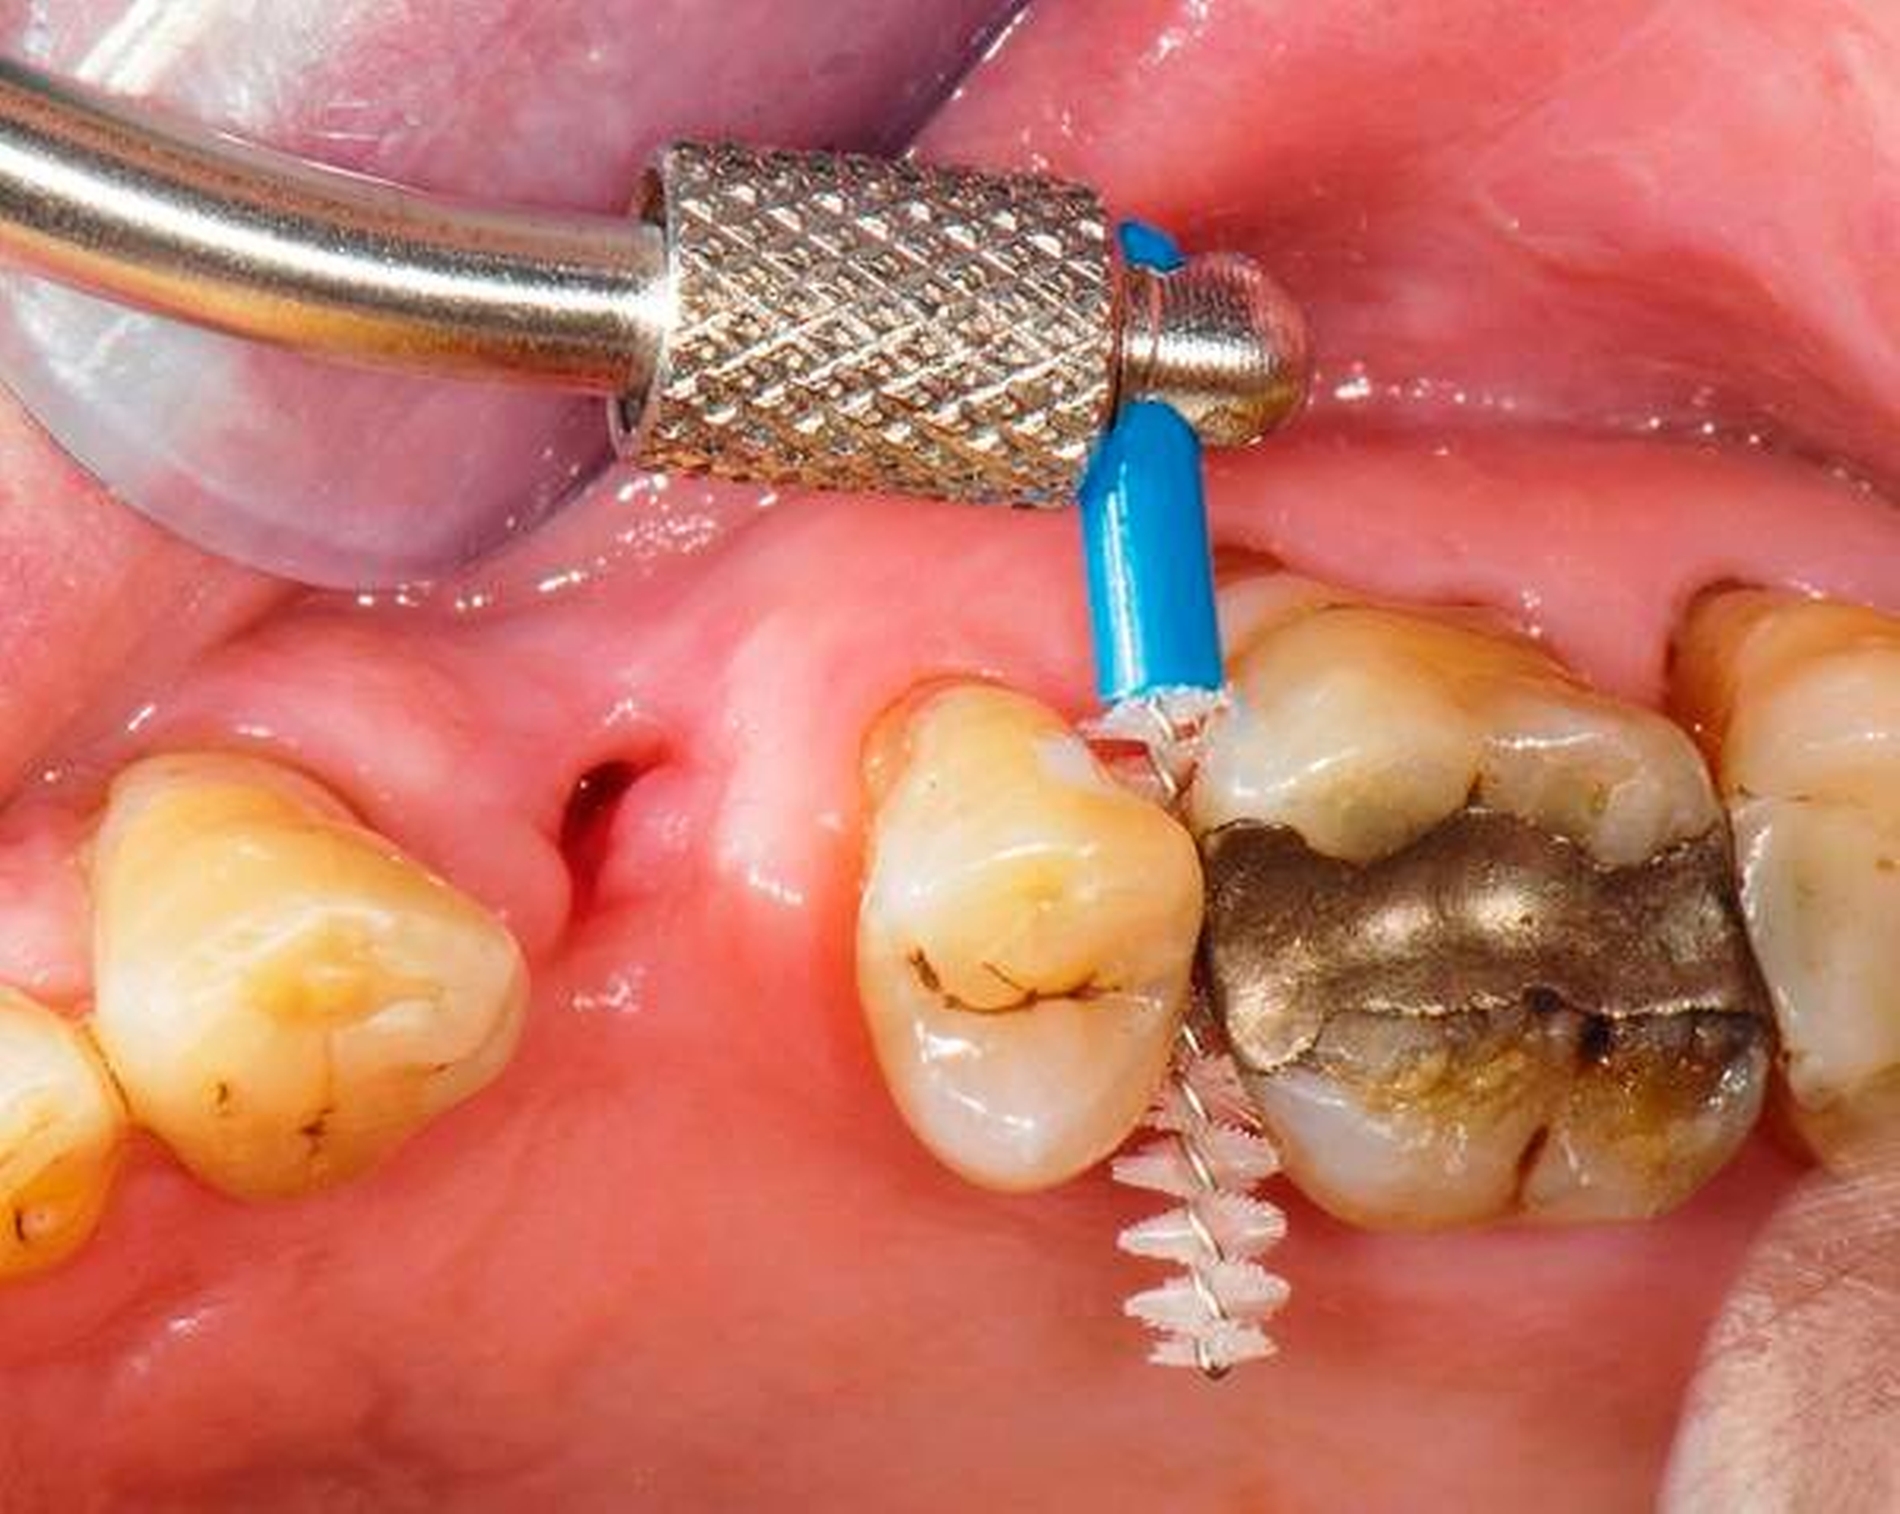

Abbildung 3: Direkte Reparatur im Seitenzahnbereich (R2-Technik)

In den Abbildungen 1 bis 3 werden Optionen für frugale Interventionen auf restaurativem Sektor aufgeführt. Es handelt sich um direkte Vollüberkronungen im Frontzahnbereich (hier: hergestellt in R1-Technik / einphasig) (Abbildung 1), direkte Teilüberkronungen im Seitenzahnbereich (hier: hergestellt in R1-Technik / einphasig) (Abbildung 2), Reparatur-Restaurationen im Seitenzahnbereich (hier: hergestellt in R2-Technik / zweiphasig) (Abbildung 3). Technische Einzelheiten zur Vorgehensweise und den Ergebnissen sind an anderer Stelle beschrieben (Literatur siehe oben).

schadensgerechte Reparaturtechniken (Abbildung 3),